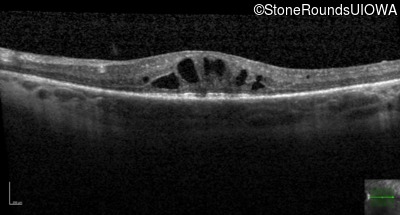

Optical Coherence Tomography - Right - 20/60 -1

Exemplar / OCT Stack